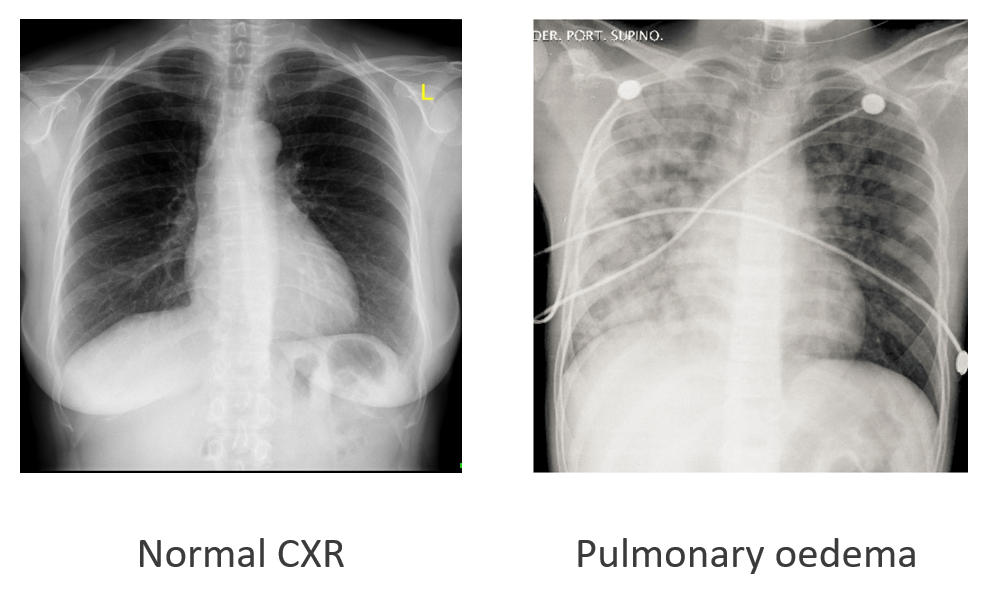

Fluid accumulation in the interstitial space

Pulmonary oedema – fluid accumulation in the interstitial spaces of the lung. Can cause;

-Hypoxia

-Dyspnoea